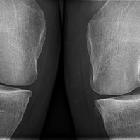

Central osteophytes, also known as subchondral or button osteophytes, are located within the joint and are thought to arise from endochondral ossification of a cartilaginous lesion .